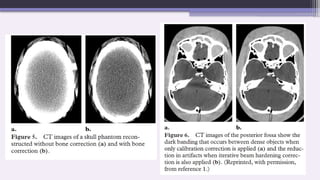

Two types of artifact can result from

this effect: so-called cupping

artifacts and the appearance of dark

bands or streaks between dense

objects in the image.

2. Streaks and Dark Bands.

In very heterogeneous cross sections,

dark bands or streaks can appear

between two dense objects in an image.

They occur because the portion of the

beam that passes through one of the

objects at certain tube positions is

hardened less than when it passes

through both objects at other tube

positions.

This type of artifact can occur both in

bony regions of the body and in scans

where a contrast medium has been used.

Dark and bright streaks radiating from

and between high-density objects, such

as dental amalgam.

Alternating dark and bright streaks in a

narrow band extending across the posterior

fossa